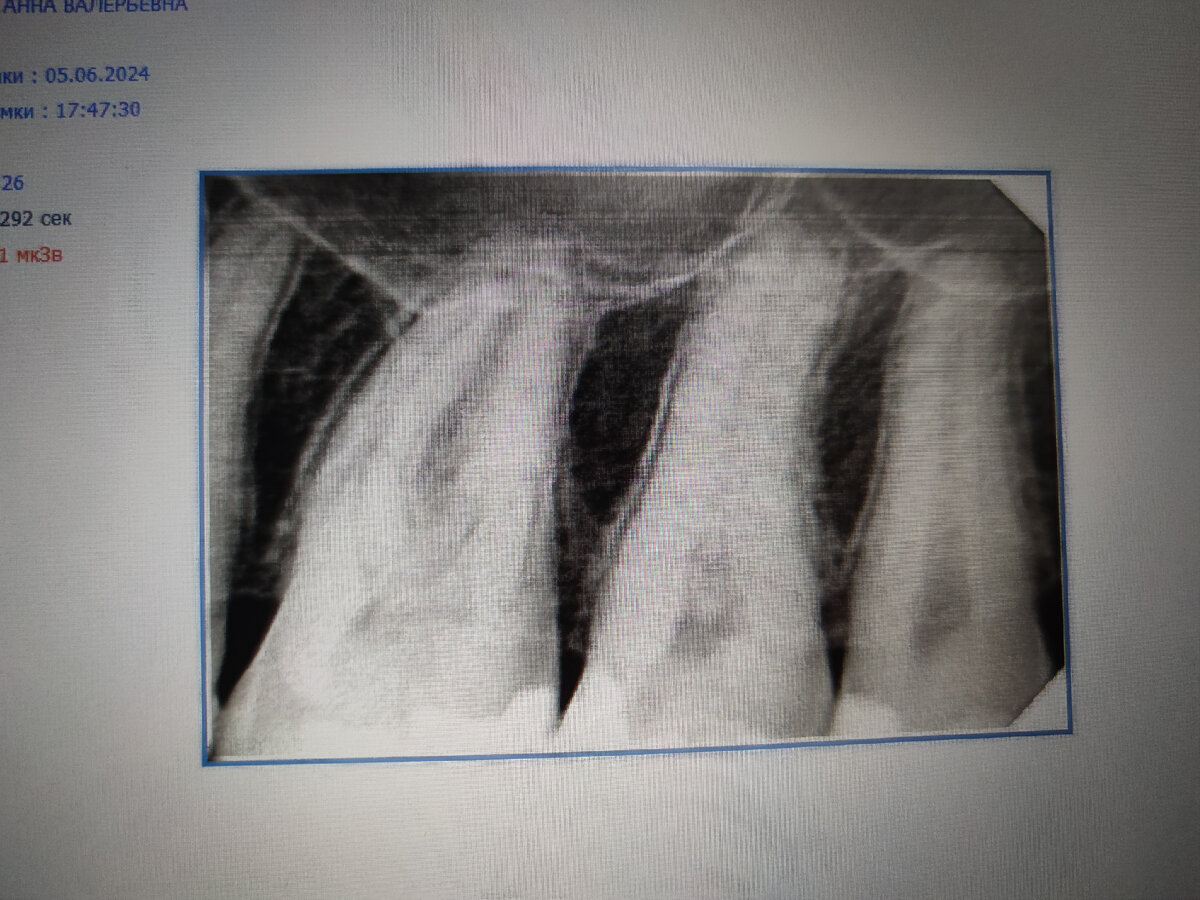

На прошлой неделе, во вторник, у меня разболелся зуб. При чем ничего не предвещало, как говорится. Сидела, никого не трогала, как вдруг появилась боль. Сначала была не сильная, ноющая, к вечеру стала гораздо сильнее. На следующий день ещё сильнее. Позвонила стоматологу, к которой хожу последние лет 20. У неё свой стоматологический кабинет. Делает хорошо и недорого. Оказалось, что у неё записи нет, уходит в отпуск. Но всё равно поехала на осмотр. При осмотре врач ничего не увидела, отправила на рентген.

Хорошо. Рентген делают в клинике, которая находится по соседству. Поэтому успела сделать снимки и принести их показать врачу.

Стоматологу не понравилась семёрка. Но делать всё равно не стала, т. к. все время расписано. Дала адреса стоматологических кабинетов, в которых работают её друзья - надёжные стоматологи.